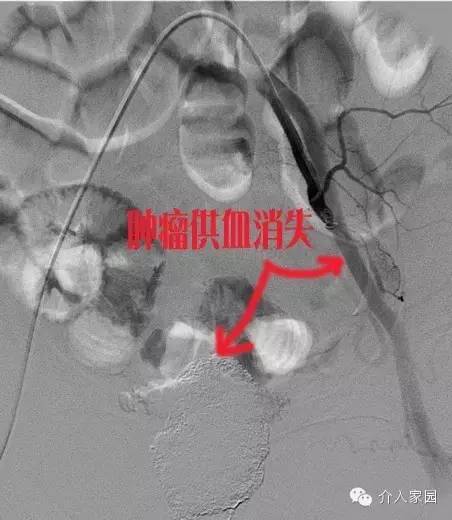

下圖是用栓塞劑把整個腫瘤供血堵死后的表現(xiàn),我們可以看到,腫瘤供血消失,患者癥狀也立即得到了好轉(zhuǎn),不再大出血了!